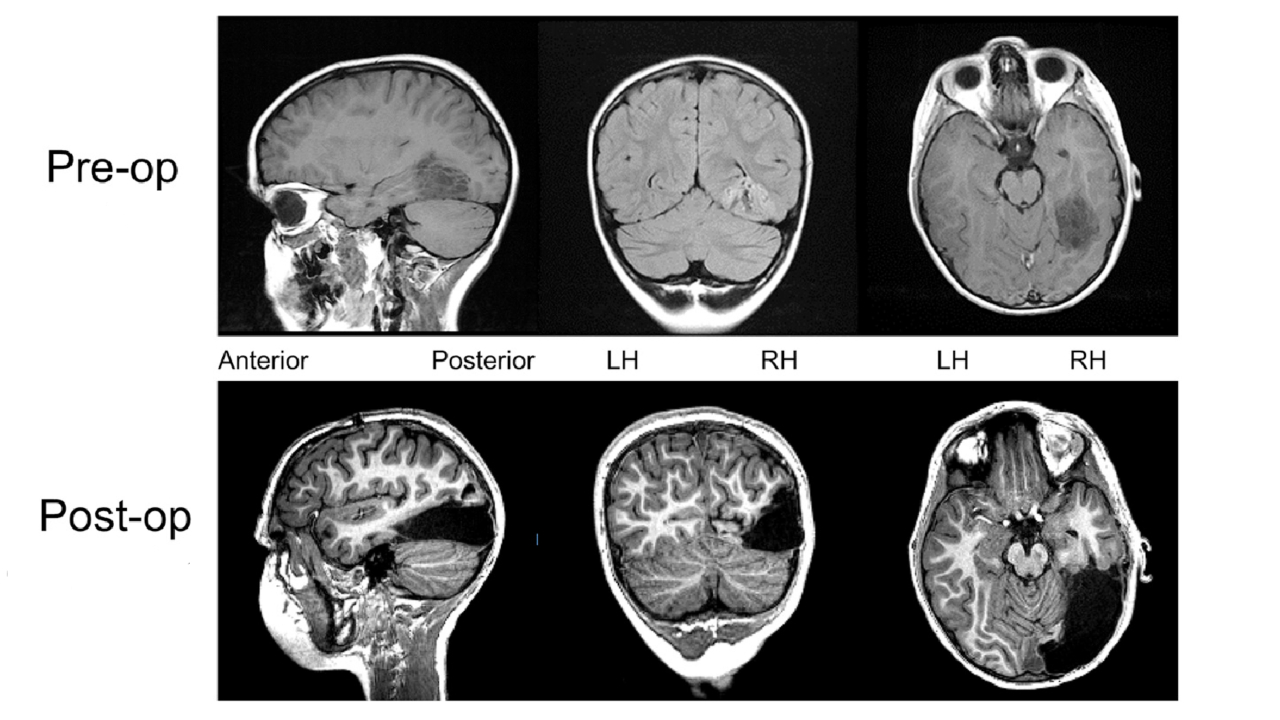

A young boy, referred to as ‘UD’ in a remarkable new report, grew up totally healthy and normal till the tender age of four, when he suffered his first seizure. His parents soon learned that he had a form of epilepsy that was uncontrollable — a consequence of a slow-growing brain tumour. He was around seven years old when his doctors and parents made a hard call — to have the tumour removed, knowing fully-well that it was nearly one-third of the right hemisphere of his brain. The two regions of his brain that the excised chunk covered were both considered indispensable for normal brain function. [caption id=“attachment_4879831” align=“alignnone” width=“1280”] MRI scans of UD’s brain before and after surgery. Modified from the publication in Cell Reports.[/caption] One was the occipital lobe, placed right at the back of the brain. It helps to process what we see, working in unison with its counterpart in the other hemisphere such that the left hemisphere process what the right eye sees, and vice versa. Along with processing visual information, the occipital lobe also helps commit these inputs to memory. An additional concern for UD’s doctors was that each of the two lobes have their key strengths — the left processes text better, while the right prevails in identifying faces. The second region to go was a chunk of his temporal lobe — a near neighbour to the occipital, and equally important. This region processes sound, linking it with other sensory information to comprehend it, and assimilating these different inputs as a composite, of sorts, in our memories. When his doctors removed both these cancerous regions in his right brain, they foresaw one of two outcomes. The first, in which his brain would not recover from the loss of these regions, leaving his visual and auditory senses severely impaired. Or a second, optimistic and slightly reaching possibility, that his brain would heal itself with other regions compensating for its lost functions, leaving his brain as a unit to function as normally as it otherwise could. Within days of his surgery, it became apparent that his doctors’ gamble was ultimately a winning one, indicated by UD’s early brain scans and cognitive tests. Apart from a permanent blind spot in his left eye’s vision that the doctors (not for lack of trying) could not correct, UD doesn’t appear to be significantly impaired at all. To the contrary, his perception of sight and sound, which the experts were most wary of him losing, appeared to be as normal as that of other kids his age. He even adjusted quickly to living with the partial blindness by compensating with wider right-eye movements. In a more recent follow-up, three years after his surgery, UD’s doctors studied blood flow in his brain using functional Magnetic Resonance Imaging (fMRI) and measured his performance on cognitive and sensory perception tests. The results found him being able to do it all — recognise faces, identify objects and silhouettes, read and understand text, distinguish sounds — just as well as he had before surgery. He even scored in the same IQ band as his pre-op self. Despite missing a sizeable portion of his brain, UD appears to have normal perception and behaviour. In their published report, his doctors themselves describe it as positively ‘dramatic’, attributing what they previously didn’t believe possible to “the power of plasticity” of the human brain’s complex network.